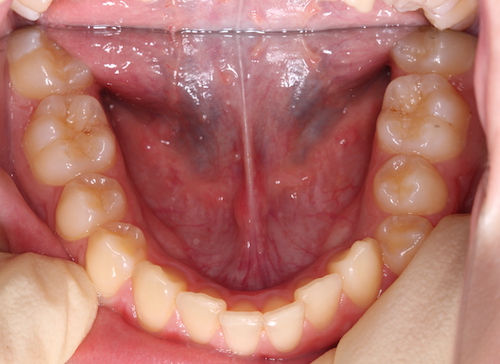

До

После